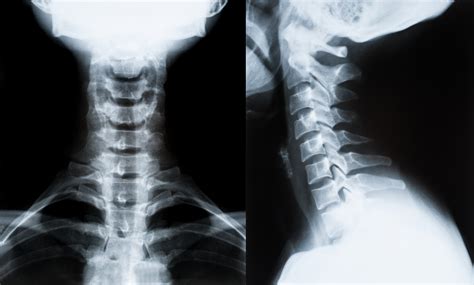

Commuters Complain About Sharp Left Side Neck Pain After Long Drives

Neck Pain After Trauma | PPT